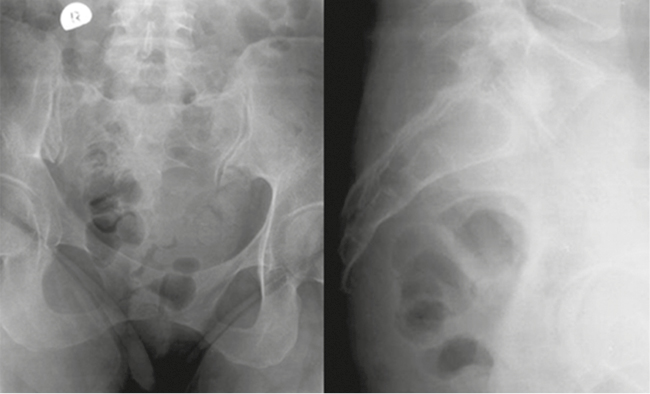

Первое клиническое наблюдение. Пациентка М., 40 лет, находилась на лечении в клинике военной травматологии и ортопедии Военно-медицинской академии им. С.М. Кирова в феврале 2016 г. Анамнез: в октябре 2015 г. получила травму копчика при падении на ягодицы; находилась на стационарном лечении в травматологическом отделении многопрофильной больницы по поводу закрытого оскольчатого перелома копчика, получала консервативную терапию; далее в течение 7 месяцев получала амбулаторное лечение по месту жительства (обезболивающие препараты, физиотерапевтическое лечение) без эффекта. В клинике у больной был выявлен несросшийся неосложненный оскольчатый перелом пятого крестцового (S5) позвонка, первого копчикового сегмента (Co1) с подвывихом копчика и болевым синдромом (рис. 1, 2). Индекс ВАШ — 8 баллов. В связи с длительно сохраняющимся болевым синдромом и неэффективностью консервативного лечения выполнена операция: резекция S5 позвонка, удаление копчика (рис. 3). Послеоперационное течение без осложнений. Пациентка выписана на 5-е сутки после операции. Значения индекса ВАШ составили через 1 месяц 2 балла, в дальнейшем — 1 балл. По шкале удовлетворенности операцией — «полностью удовлетворена».

Рис. 1. Рентгенография крестца и копчика пациентки М. до операции

Fig. 1. X-ray of the sacrum and coccyx of patient M. before surgery